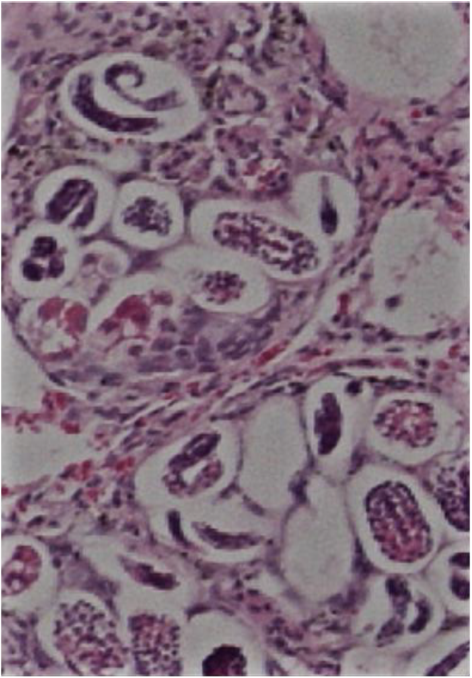

Describe the life cycle of Aelurostrongylus abstrusus

True lungworm both adults and larvae found in lungs of cats

Adults in lung parenchyma —> very small 10mm

Can lead to hyperplasia of bronchioles, alveolar ducts & pulmonary arteries if high burdens